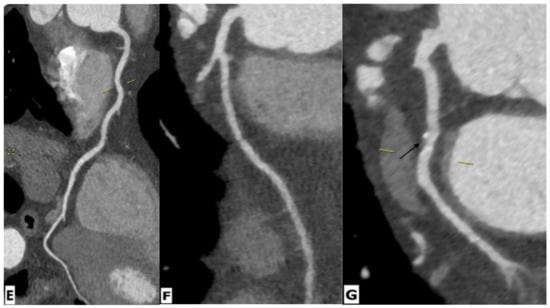

2.4. Coronary Artery Diseases

| Coronary artery disease | Raggi, P. et al. | Prospective observational study | 843 patients | CT | In a median follow-up of 2.8 years, it was seen that a CAC score of 100 was associated with 3.3-times higher odds of myocardial infarction, independent of gender and age. |

| Zanni, M.V. et al. | Cross sectional study | 101 patients and 41 controls | CTA | The study showed an increased prevalence of low-attenuation coronary plaque in HIV-positive men compared to age-matched HIV-negative healthy controls. | |

| Hoffmann, U. et al. | Cohort study | 755 HIV infected patients | CTA | Atherosclerotic plaque was seen in 49% patients. Luminal obstruction of at least 50% was rare (3%), but vulnerable plaque were more frequently observed (23%). Overall, 35% of patients demonstrated coronary artery calcium score scores greater than 0. IL-6. LpPLA2, oxLDL, and MCP-1 levels were higher in those with plaque compared to those without. | |

| Irene, J. et al. | Cross sectional study | 27 HIV infected patients | MR angiography | More than half of the subjects showed CAD with luminal narrowing detected on MR angiography. There was no association between CAD and previous cardiac conditions (viral pericarditis and zidovudine related cardiomyopathy). | |